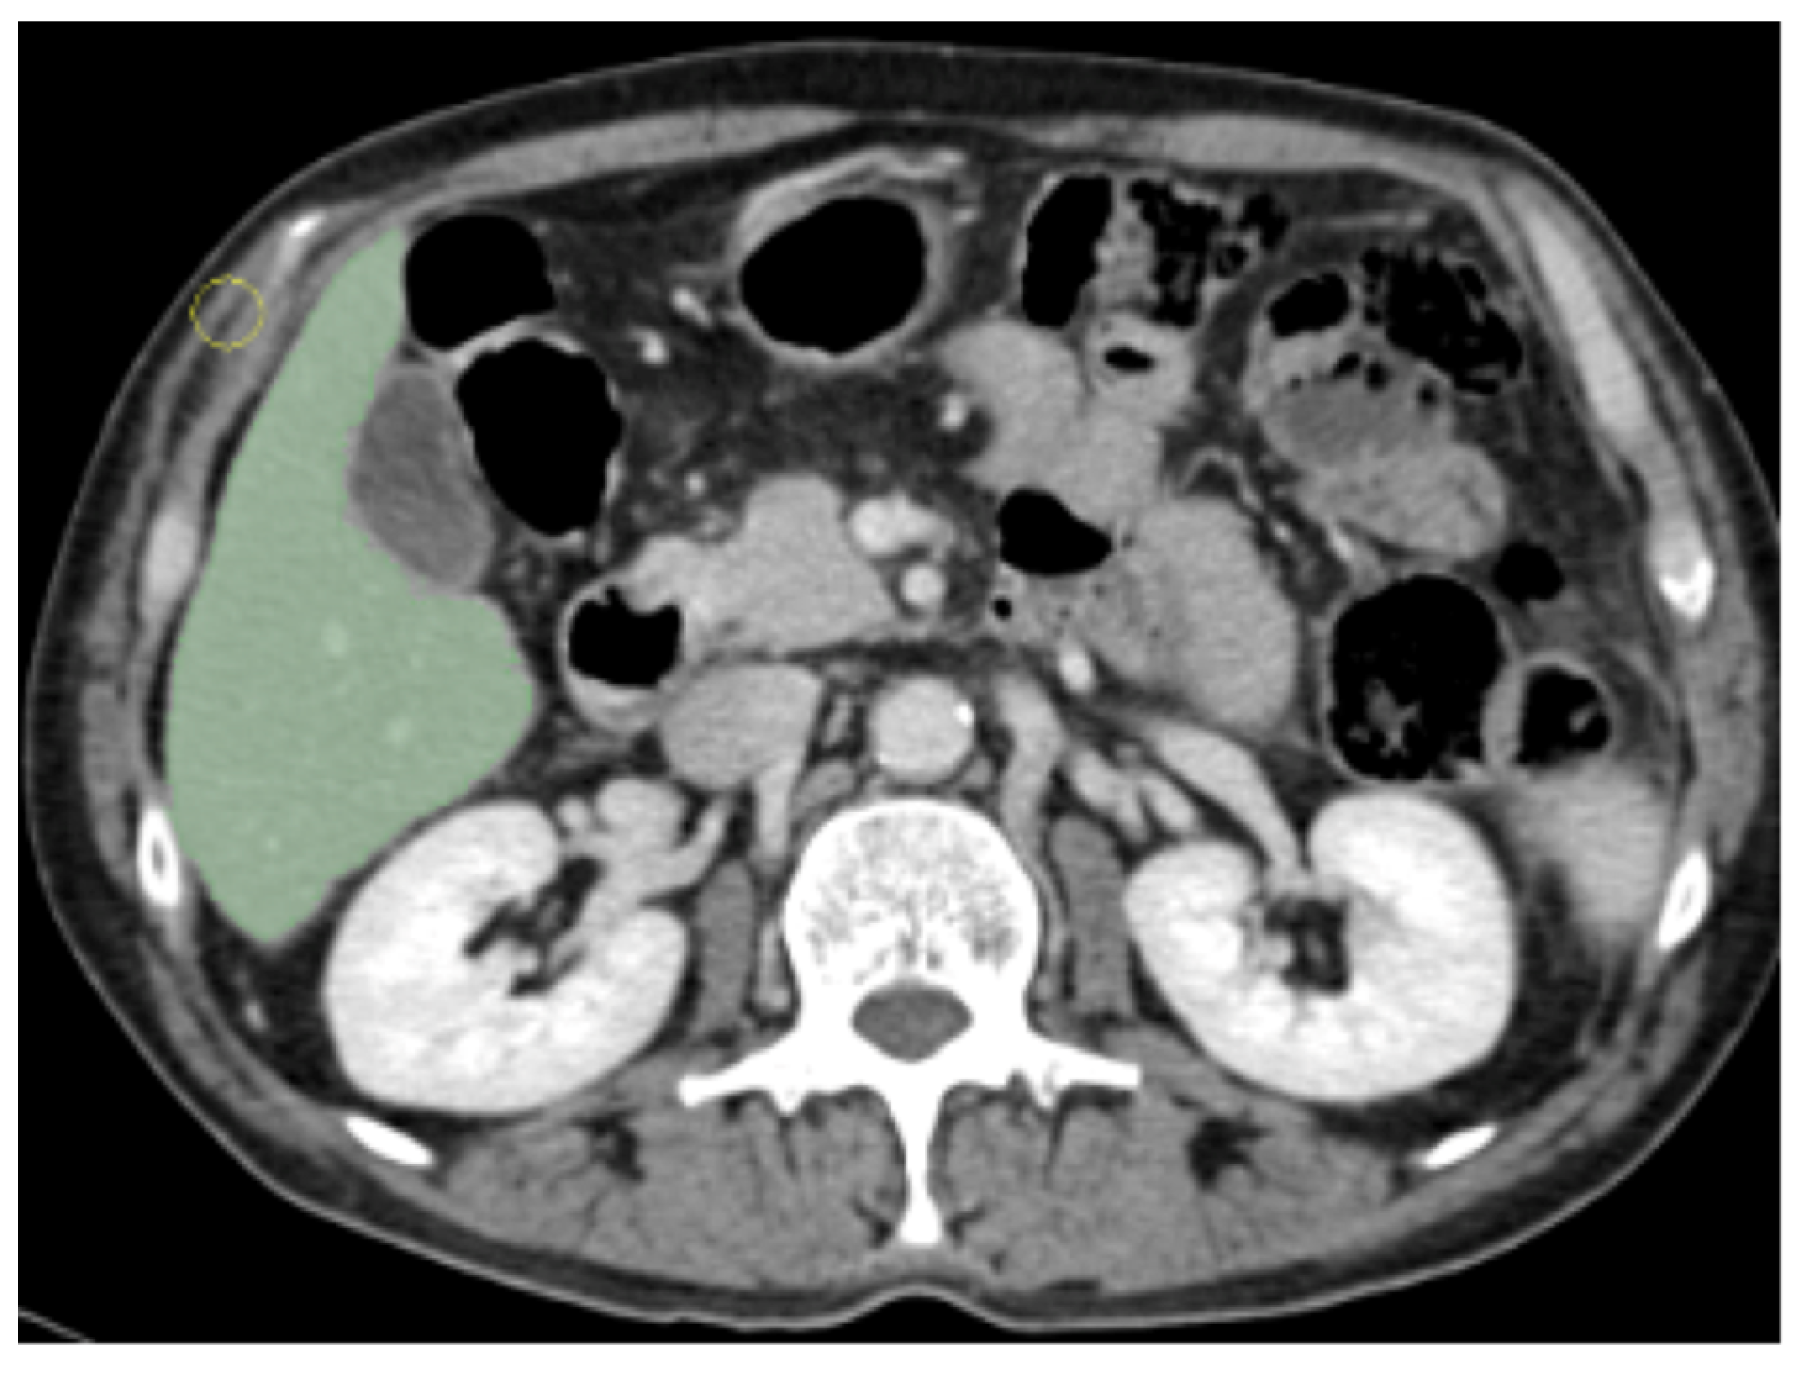

2.2. Image Acquisition and Segmentation